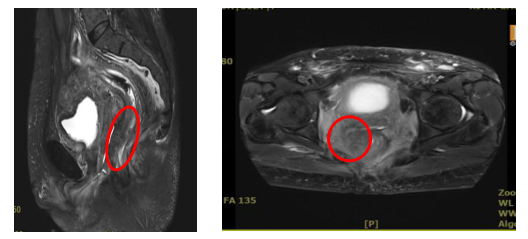

盆腔MRI提示:阴道肿瘤侵犯直肠

MRI:病变直径缩小1cm,肿瘤体积减少约50%

查体:阴道肿瘤消退,阴道壁光整部分弹性恢复,右后侧壁局限性深溃疡形成;直肠右前侧壁可触及凹陷。